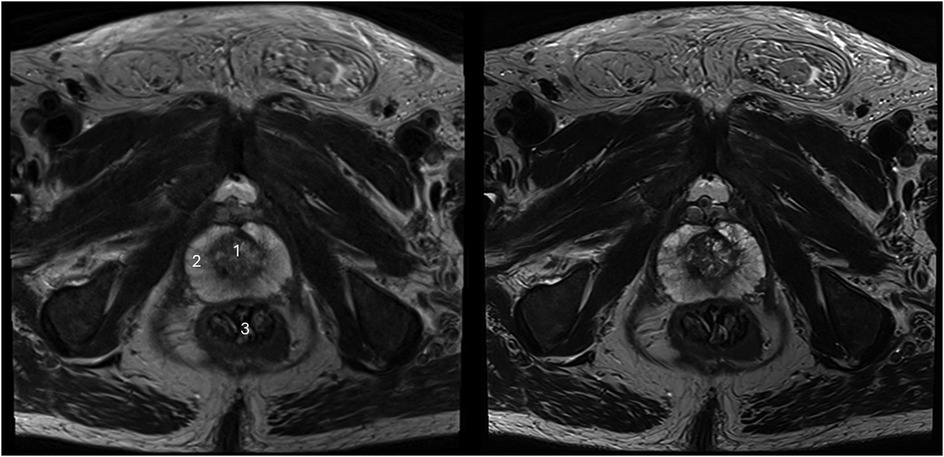

The sharpness of the prostate was evaluated to be significantly superior in T2HR compared to T2S, with medians of 5 (4–5) vs. 4 (4–4) (p < 0.001). The contours of the lesion were also rated superior, with a median of 5 (4 -5) in T2HR vs. a median of 4 (4–4) (p < 0.001). The delineation of the prostate border was also rated to be improved in T2HR [median of 5 (4–5)] as compared to T2S [median of 4 (4–5); p < 0.001]. However, the extent of the motion artifacts was evaluated to be worse in T2HR compared to T2S, with medians of 5 (4–5) vs. 5 (5–5) (p = 0.009). Please see Table 3 for the full details. Figures 2–4 show examples of both sequences.

Figure 2. Imaging of a 73-year-old man with suspicion of prostate cancer. T2S on the left-hand side and deep learning-reconstructed T2HR on the right-hand side. T2HR demonstrates a sharper depiction of the anatomical details and improved delineation of the transition and peripheral zones. The mpMRI was rated as PI-RADS 2 by both readers. (1) Transition zone of the prostate; (2) Peripheral zone of the prostate; (3) Rectum.